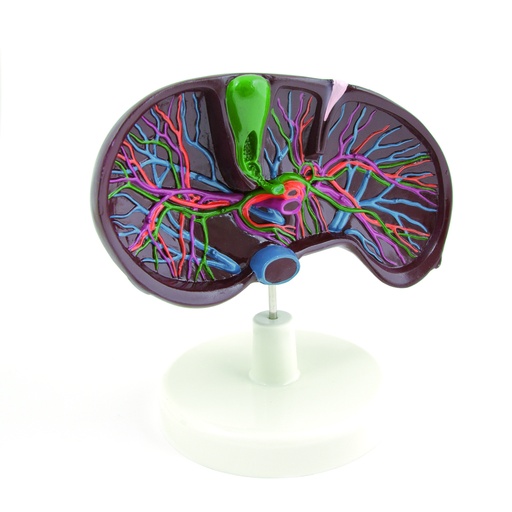

HEINESCIENTIFIC Anatomisches Modell Leber mit umliegenden Strukturen

Anatomisches Modell der Leber und ihrer umliegenden Strukturen

Das Modell Leber mit Pankreas zeigt die Leber mit ihren umliegenden Strukturen. Neben der Bauchspeicheldrüse und der Gallenblase sind auch die zu- und abführenden Gefäße dargestellt. Mit Stativ auf Kunststoffsockel montiert. Aufwändig koloriertes anatomisches Modell.

Dargestellte Organe und Strukturen

- Rechter und linker Leberlappen

- Ligamentum falciforme

- Area nuda

- Lig. teres hepatis

- Leberpforte

- Gallenblase

- Ductus cysticus

- Ductus hepaticus

- Ductus choledochus

- Aorta

- A. mesenterica superior

- V. mesenterica superior

- A. linealis

- A. hepatica

- Pankreas

- Ductus pancreaticus

- Zwölffingerdarm (nur teilweise dargestellt)

Produktdaten:

Circa lebensgroß

Nicht zerlegbar

Maße: 35 x 22 x 15cm

()

42,48 € 42.48 EUR